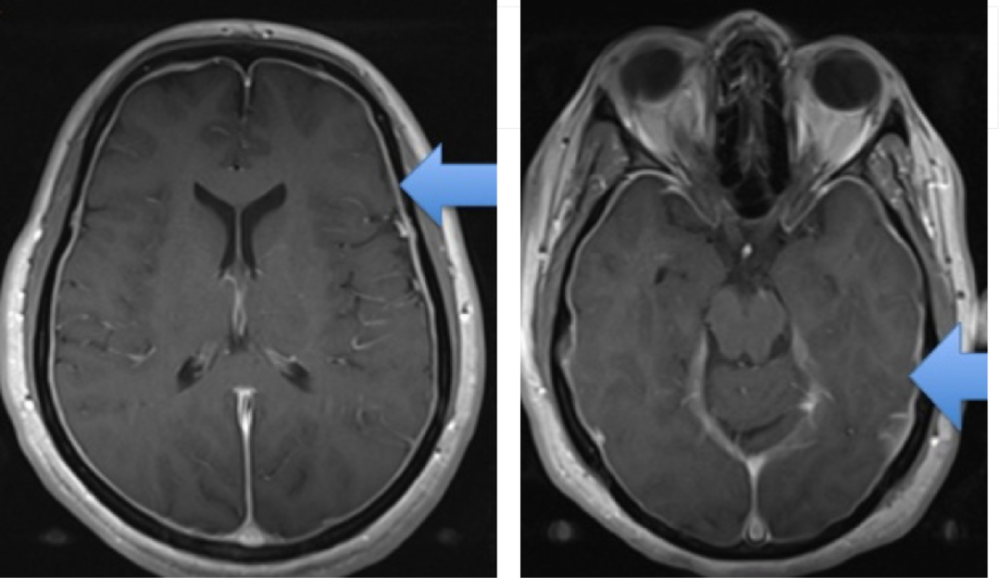

起床后突然头痛原来是低颅压综合征

脑卒中影像学鉴别诊断(一):灰质白质改变

一文理清:脑膜强化的常见类型与鉴别诊断